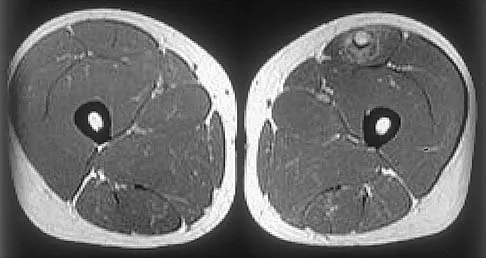

A 53-year-old man has a 4- x 5-cm high-grade soft-tissue sarcoma in the midthigh. As part of the staging evaluation, regional nodes should be assessed by